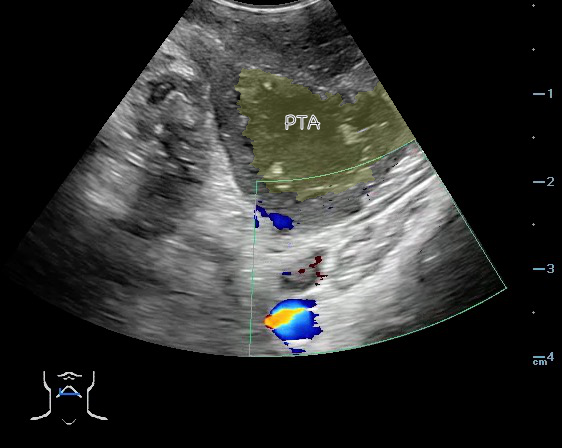

- Peritonsillar abscess is visualized as a hypoechoic or complex cystic structure

- Ultrasound-guided needle aspiration of a PTA:

- Figure 45. and 46. PTA aspiration

- The carotid artery is seen as an anechoic tubular structure along the posterolateral aspect of the tonsil on ultrasound. Its relationship to the abscess cavity should be determined. Color Doppler can help locate the carotid artery.

- Figure 47 and 48. PTA with color Doppler of carotid artery